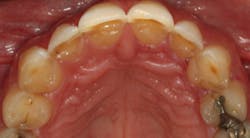

From the two-dimensional evaluation, the signs of occlusal instability were clear. Darren had very thin, chipping incisal edges, to the point where they were becoming transparent. The patient had almost worn shelves into the lingual of the maxillary anteriors, suggesting a restricted envelope of function. He also had wear into dentin in the anterior teeth as well as posterior teeth, and his anterior teeth had Class 1 mobility.

In addition, Darren failed The Dawson Academy’s five requirements of occlusal stability:

- Stable and equal intensity stops on all teeth in centric relation

- Anterior guidance in harmony with the envelope of function

- All posterior teeth disclude during mandibular protrusive movement

- All posterior teeth disclude on the nonworking side during mandibular lateral movement

- All posterior teeth disclude on the working side during mandibular lateral movement

Luckily, the patient was a Piper TMJ Classification 1 with healthy intact joint assembly. His functional problems were primarily occlusal-muscle. But the dentition also exhibited signs of acid corrosion in a presentation that suggested gastroesophageal reflux disease (GERD), so we referred Darren to his physician where he was treated for GERD prior to starting any dental treatment.